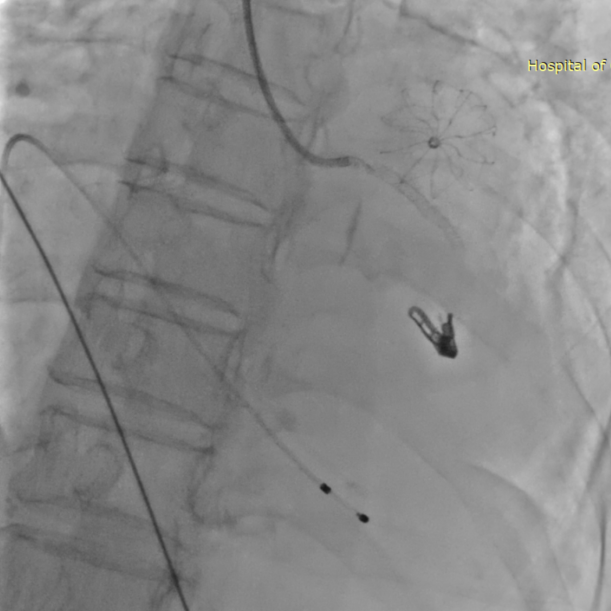

患者全麻下行TEER手术。向睿副主任团队穿刺患者右侧股静脉,在X线及食道超声指导下完成房间隔穿刺(视频4)成功获得3.95cm穿刺高度(图4)。再将加硬导丝送至左上肺静脉,20F股静脉扩张鞘充分扩张股静脉穿刺部位,沿加硬导丝将可操纵导引导管(SGC)送入左房。延SGC送入XTR夹子完成骑跨,使用M旋钮使夹子指向二尖瓣(图5)(视频5)。调整Mitraclip输送系统顺利到达二尖瓣目标位置,TEE指导下左房内完成弹道测试和Orientation调整(视频6)。缓慢将XTR夹子送入左室,并三维再次确认夹子轴向和反流位置,缓慢上提夹子使夹臂成功捕获瓣叶(视频7),Gripper Down夹持前后瓣叶并缓慢关闭夹臂(视频9),夹持后反流降至微量(视频10),二尖瓣平均跨瓣压差2mmHg(图6)。评估后将夹子释放。释放后反流微量夹子稳定。术后复查超声证实夹合组织充分,显示微量残余分流。术后二尖瓣平均跨瓣压差2mmHg,肺静脉多普勒波形恢复正常。手术时间持续约1.5小时。

图7:夹子释放